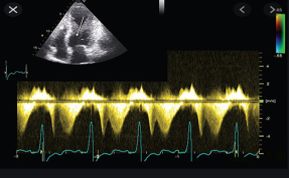

Ecocardiograma transtoracico con el mejor equipo de la región

Ecocardiogframa estres

• Ecocardiografía